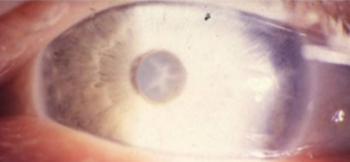

glaucomflecken

diagnosis of previous acute angle closure glaucoma

small gray-white anterior subcapsular or capsular opacities w/in pupillary zone

no visual loss